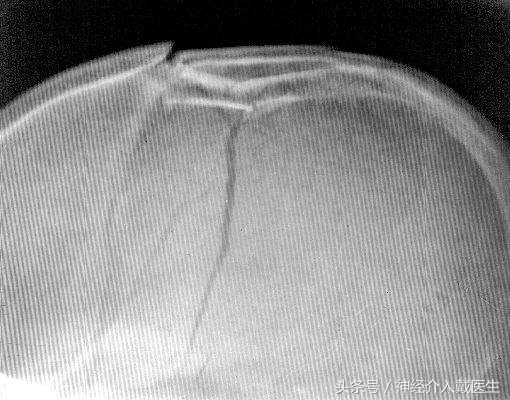

颅骨骨折的分类 按颅骨骨折的部位,可分为颅盖骨折及颅底骨折。根据骨折的形态不同,又可分为:线形骨折、凹陷骨折、粉碎骨折、洞形骨折及穿透性骨折。

此外,按骨折的性质,视骨折处是否与外界相通,又分为闭合性骨折及开放性骨折,后者包括颅底骨折伴有硬脑膜破裂而伴发外伤性气颅或脑脊液漏者。 单纯的线形骨折本身无需特殊处理 ,

其重要性在于因骨折而引起的脑损伤或颅内出血,尤其是硬膜外血肿,常因骨折线穿越脑膜中动脉而致出血。因此,凡有骨折线通过上矢状窦、横窦及脑膜血管沟时,皆应密切视察、及时作可行的辅助检查,以免贻误颅内血肿的诊断。 线形骨折常伴发局部骨膜下血肿,尤以儿童较多。当骨折线穿过颗肌或枕肌在颠骨或枕骨上的附着区时,可出现颞肌或枕肌肿胀而隆起,这一体征亦提示该处有骨折发生。